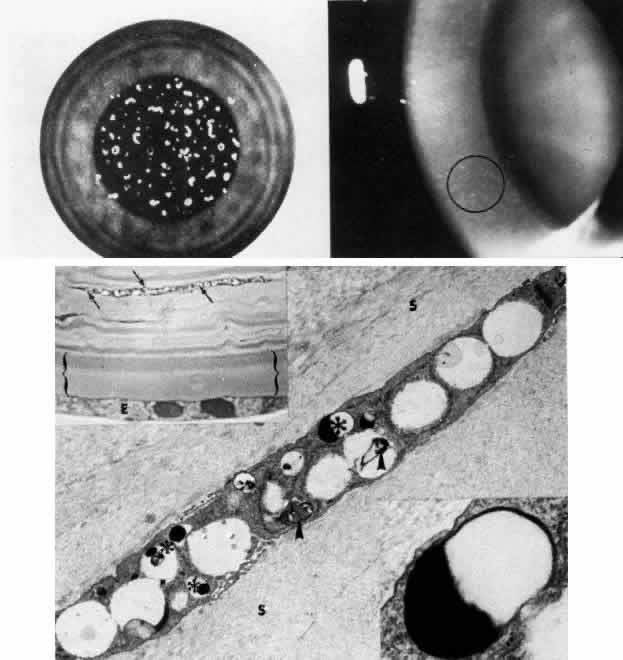

Macular Dystrophy (Groenouw Type II)

Among the classic corneal dystrophies, macular dystrophy, unlike granular and lattice dystrophies, is an autosomal recessive disorder and is far less common. It usually begins in the first decade of life and leads to progressive visual deterioration as the stroma becomes generally cloudy, with superimposed dense, gray-white spots (Figs. 5 AND 11; Color Plate 1H). Unlike granular dystrophy, these macular spots have indefinite edges and the intervening stroma is not clear. Young patients exhibit axial lesions in the superficial layers of the cornea, but with time, lesions approach the periphery and extend throughout the entire stromal thickness. Corneal thinning confirmed by central pachymetry has been documented.129 Also unique is primary involvement of the endothelium as evidenced clinically by the presence of guttate changes of Descemet's membrane.

Fig. 11. Macular corneal dystrophy. Top left. Clinical appearance of cornea features diffuse haze extending to the limbus with superimposed, dense gray-white spots. Bottom left. Light photomicrograph of posterior cornea shows endothelial cells staining intensely positive for acid mucopolysaccharide. Guttate excrescences (*) of Descemet's membrane (DM) are frequent. The stroma also shows positive staining for acid mucopolysaccharide both diffusely extracellularly and intensely within keratocytes (circled) (colloidal iron × 500). Right. Transmission electron micrograph discloses typical fibrillary granular deposits within keratocytes (K), throughout the posterior layer of Descemet's membrane, and within the endothelial cells (En). The anterior banded region of Descemet's membrane (bracketed) is not affected (× 3500).

The lesions in macular corneal dystrophy stain intensely with alcian blue and colloidal iron, minimally with PAS, and not at all with Masson's trichrome. Birefringence is decreased. The lesions have been histochemically identified as an abnormal keratan sulfate-like glycosaminoglycan that accumulates extracellularly within the stroma and Descemet's membrane and intracellularly within keratocytes and endothelium.130

As would be typical of an autosomal recessively inherited condition, macular dystrophy presumably results from deficiency of a hydrolytic enzymes (sulfotransferase) and may thus be considered a localized mucopolysaccharidosis.131 The effect of altered glycosaminoglycan metabolism is evident at the cellular level; on transmission electron microscopy, keratocytes and endothelial cells exhibit distention of rough-surfaced endoplasmic reticulum cisternae. With the acridine orange technique, compensatory generalized hyperactivity of the lysosomal enzyme system has been demonstrated.132 Eventually the accumulated undigested storage products engorge the cells, and the cells ultimately degenerate or rupture. The derivation of these intracytoplasmic storage vacuoles from endoplasmic reticulum suggests that the biochemical lesion in macular dystrophy occurs at a different metabolic location than in the systemic mucopolysaccharidoses, since in the latter, storage products accumulate within lysosomelike intracytoplasmic vacuoles associated with the Golgi complex.133 Snip and associates134 were able to determine that the storage phenomenon affecting endothelium and Descemet's membrane is likely also primary, since the intracellular and extracellular lesions appear ultrastructurally comparable to those evident in the keratocytes and stroma.